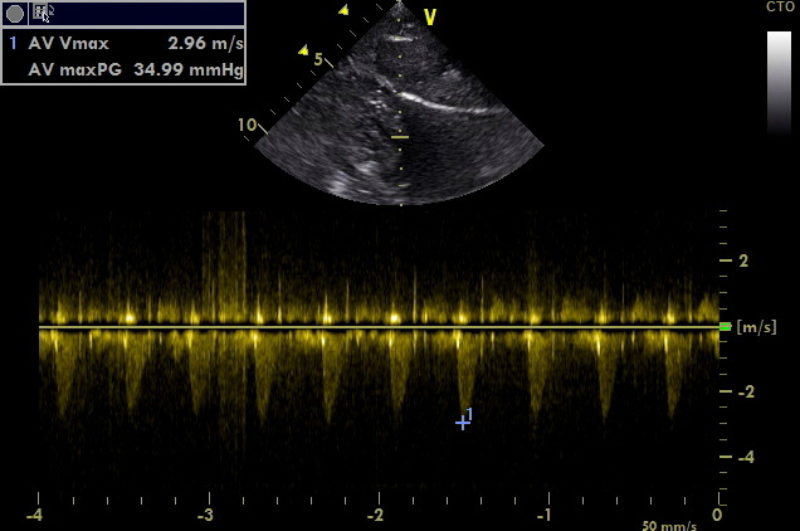

Bei der ersten Herzultraschalluntersuchung war Mailow fünf Monate alt. Dabei wurde im linksventrikulären Ausflusstrakt vor der Aortenklappe eine Einengung festgestellt. Es wurde eine geringgradige Subaortenstenose (SAS) diagnostiziert. Aortenstenosen verschlimmern sich häufig im Laufe des Wachstums, daher sollten auf jeden Fall auch bei anfänglich geringgradigen Befunden Folgekontrollen durchgeführt werden. Mailows Befund blieb relativ stabil. Bei seiner letzten Untersuchung war Mailow fast drei Jahre alt.  Man maß in der Aorta eine maximale Blutflussgeschwindigkeit von 3 m/s (dies entspricht einem Druckgradienten von 36 mmHg). Bei gesunden Hunden ist die Blutflussgeschwindigkeit in der Aorta in der Regel unter 1,8 m/s (entspricht ca. 13 mmHg). Mit Hilfe der Flussgeschwindigkeit beziehungsweise des Druckgradienten kann man den Schweregrad der Aortenstenose einteilen.